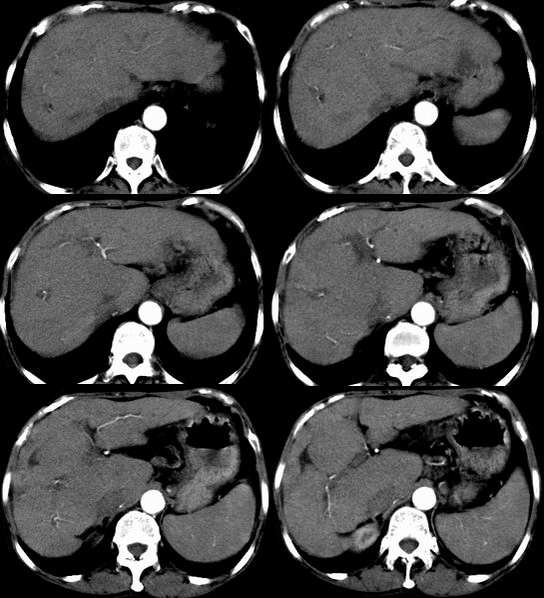

患者,女,53岁。恶心、上腹痛、下腹胀、消瘦2月余。曾有肝硬化、乙肝、胆囊炎病史。

b超发现肝右叶实质性占位,做ct检查。

平扫

此病灶不具备典型小肝癌的强化方式,从动脉期及静脉期看病灶是呈逐渐强化。

结合病史及b超表现,考虑肝癌合并脂肪变性可能大。平扫病灶密度较一般常见肝癌密度偏低,增强动脉期强化不明显,但长期的肝炎及肝硬化病史,不能不考虑肝癌的可能性,合并脂肪变性,病灶强化的程度就会明显减低。建议必要时mri三期增强扫描。